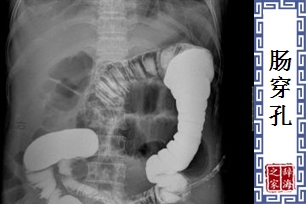

- 病名。肠壁穿破成孔,粪便等排泄物流入腹腔,导致感染。症状包括呕吐、剧烈的腹痛、脉搏微弱等。

【肠穿孔】 图片鉴赏